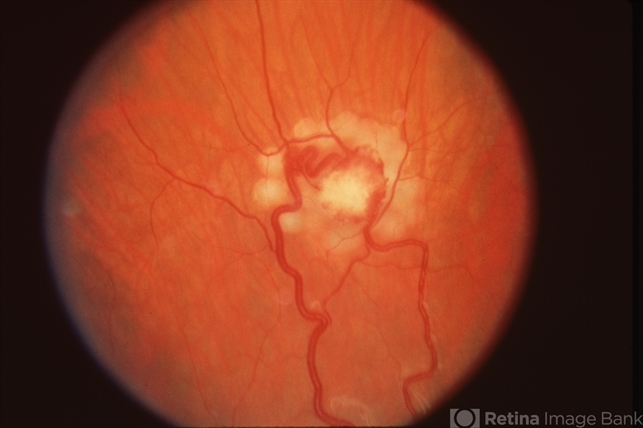

- VON HIPPEL

- Von Hippel-Lindau, retinal angioma, laser photocoagulation

- Fundus camera

- Fundus photo immediately after laser photocoagulation treatment of the retinal angioma OD in Von Hippel-Lindau.